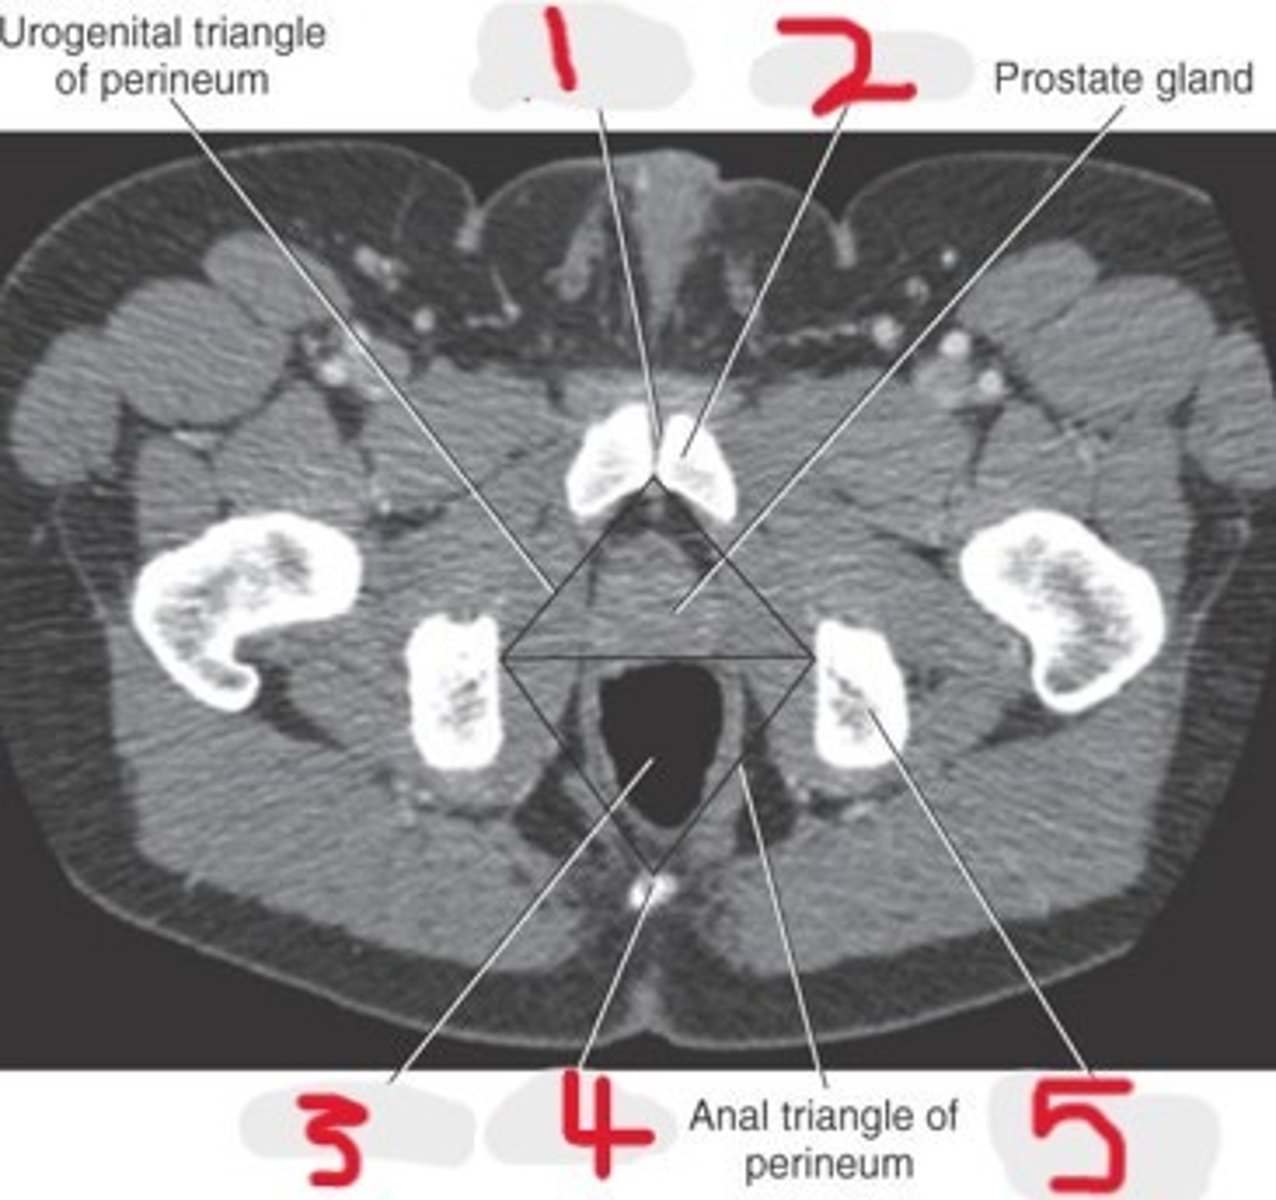

1) Pubic symphysis

2) Pubic bone

3) Prostate gland

4) Rectum

5) Coccyx

6) Ischial tuberosity

Name all numbered structures